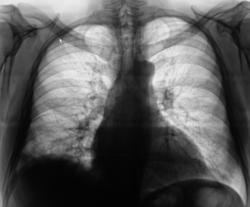

Пациент был направлен в рентгеновский кабинет терапевтом с диагнозом "Правостороняя пневмония". Было произведено стандартное исследование.

Было назначено противовоспалительное лечение. Через 1 неделю проведен "рентген-контроль".